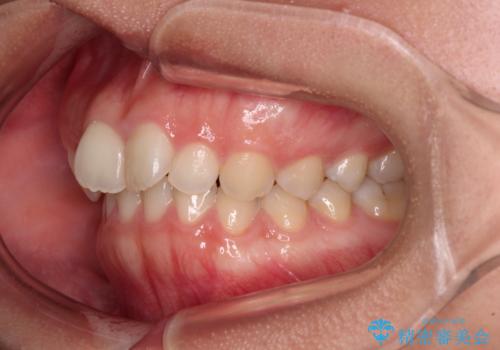

- 上の前歯が前方に飛び出していることを気にして来院された患者様です。

奥歯の咬み合わせをチェックすると、上顎歯列が相対的に前方に位置しているため、補助装置を用いて上顎歯列を確実に後方に移動させ、インビザラインで歯列を整えて行くこととしました。

インビザライン単体でも同様の結果が得られる可能性がありますが、万が一奥歯がうまく後方移動できなかった場合、リカバリーが非常に大変となるため、事前に補助装置を併用して確実に結果が得られるように工夫をしています。